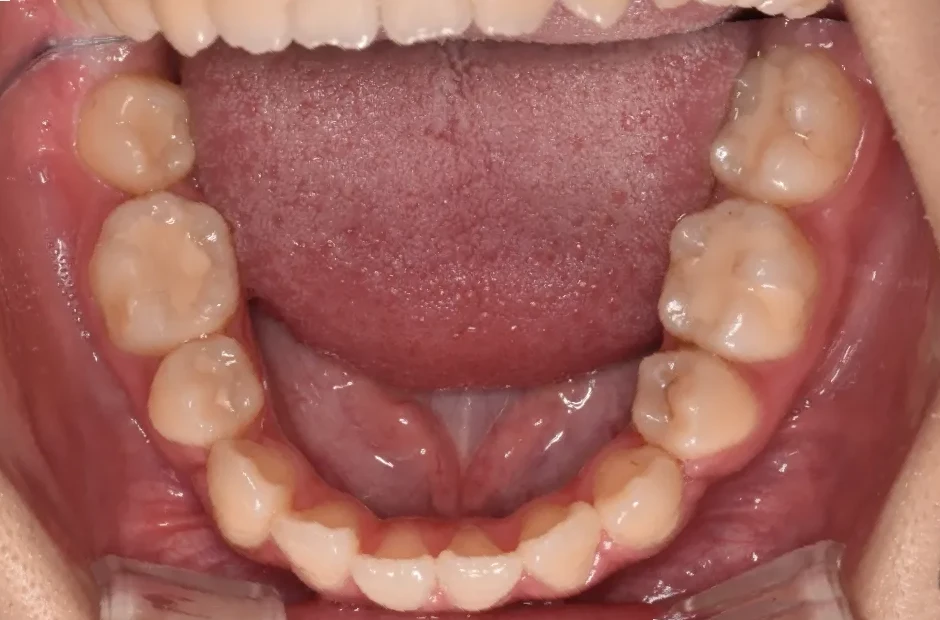

叢生

| 診断名・主訴 | 叢生 |

|---|---|

| 年齢・性別 | 43歳・女性 |

| 治療期間・回数 | 2年7か月 27回 |

| 治療に用いた主な装置 | 舌側矯正 |

| 抜歯部位 | 両顎4,4 |

| 治療費 | 100万円(税抜) |

| リスク・副作用 | 装置による違和感・疼痛・歯肉退縮・歯根吸収・虫歯のリスクなど |

治療前

治療後